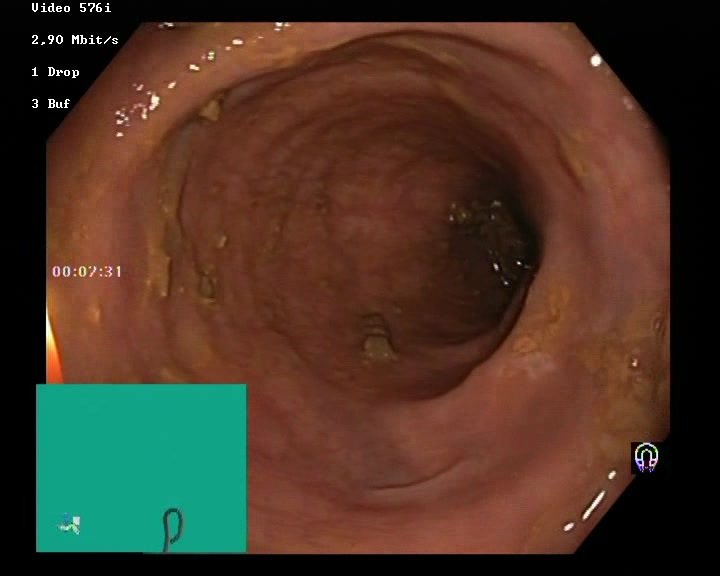

The Nerthus Dataset

BBPS 3

BBPS 2

BBPS 1

BBPS 0